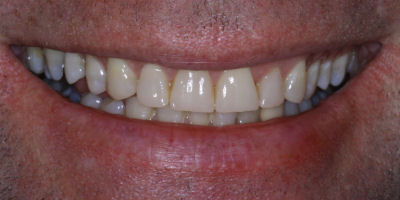

Repair Worn Teeth